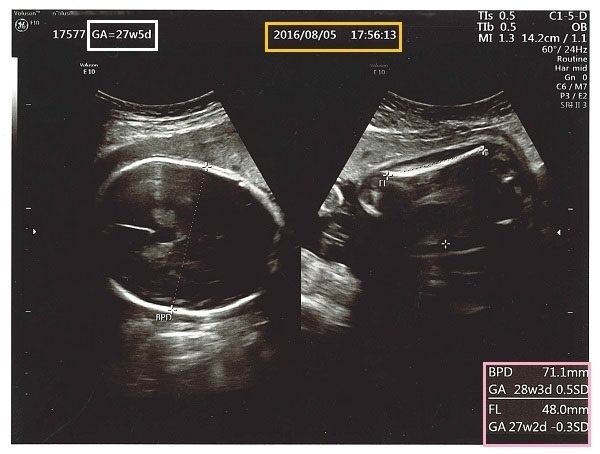

妊娠中期の超音波画像~その1~

これは妊娠中期の超音波画像で、左側に赤ちゃんの頭、右側に赤ちゃんの太ももの部分が写っています。真ん中のオレンジ色の四角の部分は、超音波検査をした日付け、左の白い四角の部分が超音波検査をした日の在胎週数になります。

右端のピンク色の四角の中には計測値が出ています。「BPD」は、児頭大横径(じとうだいおうけい)で、赤ちゃんの頭の一番長い横幅部分の値、「FL」は大腿骨長(だいたいこっちょう)で、赤ちゃんの太ももの骨の長さの値です。

それぞれの値の下にある「GA」は、計測値がどの在胎週数に相当するのかが出ています。この値で赤ちゃんが実際の妊娠週数に対して順調に成長しているのか、それとも小さいのかあるいは大きいのかを先生は見ています。